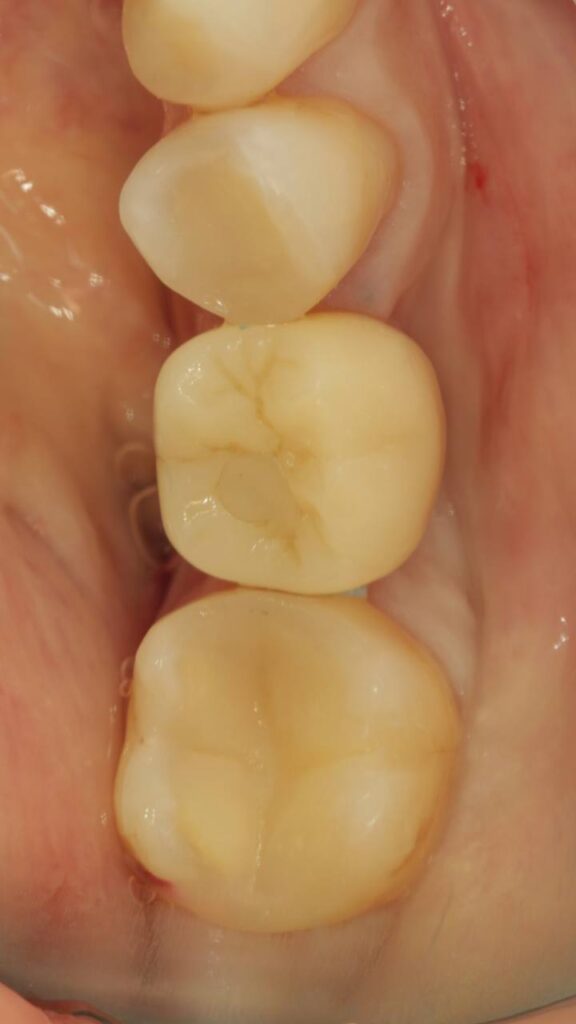

Протезирование коронками из диоксида циркония, после эндодонтического лечения — Исламов Л.А.(01.04.2026)